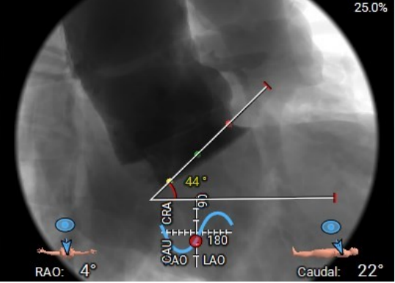

术前主动脉CTA评估:主动脉瓣三叶式,瓣叶基本等大,瓣叶稍增厚,左右瓣叶游离缘轻微钙化;主动脉瓣环周长折算直径约27.6mm;双侧冠脉开口高度可LCA:13.7mm,RCA:17.3mm;左侧冠脉轻度钙化;术中建议造影角度RAO:4°,CAU:22°;降主动脉及双侧髂总动脉轻微钙化,走行迂曲;双侧髂总动脉稍增宽;双侧髂外动脉迂曲。

右窦居中位:LAO:4° CAU:22°

主动脉瓣环夹角:44°